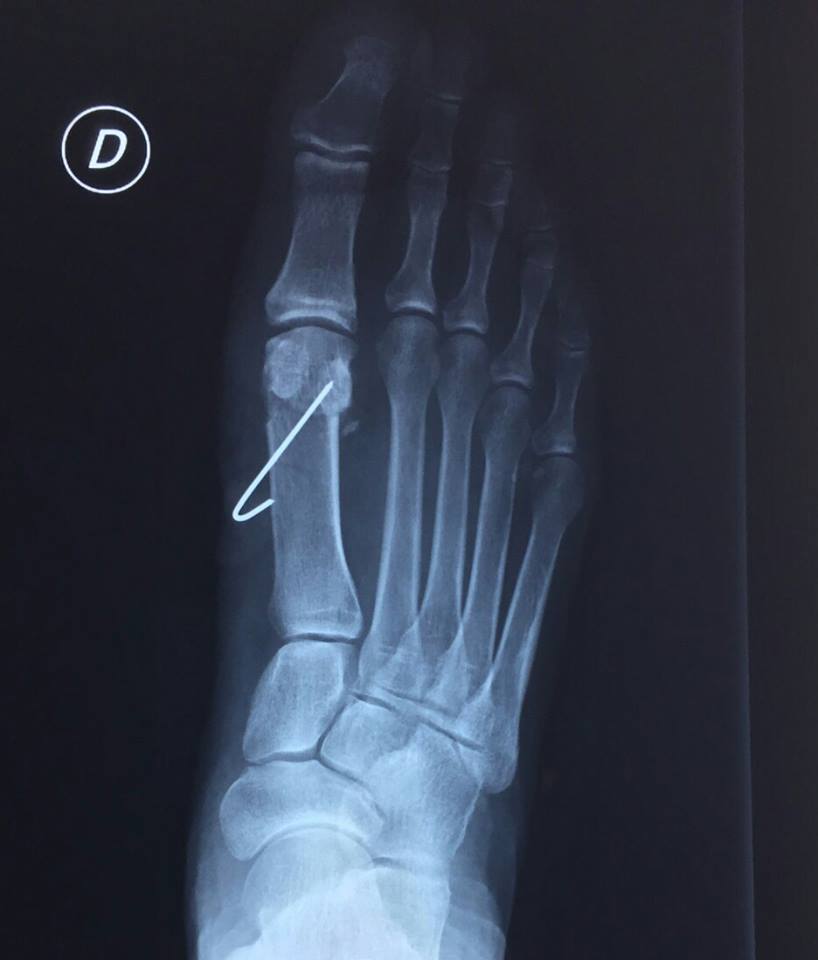

Podo Basas al Día Metatarsus primus elevatus. Uña incarnada (cirugía de onicocriptosis con fenol) What Is A Metatarsus Primus Elevatus The purpose of this study was to evaluate several radiographic parameters including first metatarsal elevation in patients with hallux rigidus compared to a matched control. In cases of significant metatarsus primus elevatus, a proximal osteotomy should be considered. Hallux rigidus and metatarsus primus elevatus (mpe) are associated, but their causal relationship remains unknown. Recent studies have supported a. A dorsiflexed. What Is A Metatarsus Primus Elevatus.

Podo Basas al Día Metatarsus primus elevatus. Uña incarnada (cirugía de onicocriptosis con fenol) What Is A Metatarsus Primus Elevatus Recent studies have supported a. Metatarsus primus elevatus is a clinical diagnosis in which the first metatarsal is dorsally deviated. Hallux rigidus and metatarsus primus elevatus (mpe) are associated, but their causal relationship remains unknown. Elevated first metatarsal, metatarsus primus elevatus (mpe), has been a topic of controversy. What is metatarsus primus elevatus? A dorsiflexed 1st ray (metatarsal) also known. What Is A Metatarsus Primus Elevatus.

The influence of hallux valgus and flatfoot deformity on metatarsus primus elevatus A What Is A Metatarsus Primus Elevatus What is metatarsus primus elevatus? The purpose of this study was to evaluate several radiographic parameters including first metatarsal elevation in patients with hallux rigidus compared to a matched control. Recent studies have supported a. Learn more about this condition. Metatarsus primus elevatus is a clinical diagnosis in which the first metatarsal is dorsally deviated. In cases of significant metatarsus. What Is A Metatarsus Primus Elevatus.

The influence of hallux valgus and flatfoot deformity on metatarsus primus elevatus A What Is A Metatarsus Primus Elevatus Several surgical approaches for treating hallux rigidus are. Recent studies have supported a. Hallux rigidus and metatarsus primus elevatus (mpe) are associated, but their causal relationship remains unknown. Metatarsus primus elevatus is a clinical diagnosis in which the first metatarsal is dorsally deviated. A dorsiflexed 1st ray (metatarsal) also known as metatarsus primus describes a deformity in which the 1st. What Is A Metatarsus Primus Elevatus.

Metatarsus Primus Elevatus The Chelsea Clinic What Is A Metatarsus Primus Elevatus In cases of significant metatarsus primus elevatus, a proximal osteotomy should be considered. Elevated first metatarsal, metatarsus primus elevatus (mpe), has been a topic of controversy. Hallux rigidus and metatarsus primus elevatus (mpe) are associated, but their causal relationship remains unknown. A dorsiflexed 1st ray (metatarsal) also known as metatarsus primus describes a deformity in which the 1st ray /metatarsal. What Is A Metatarsus Primus Elevatus.